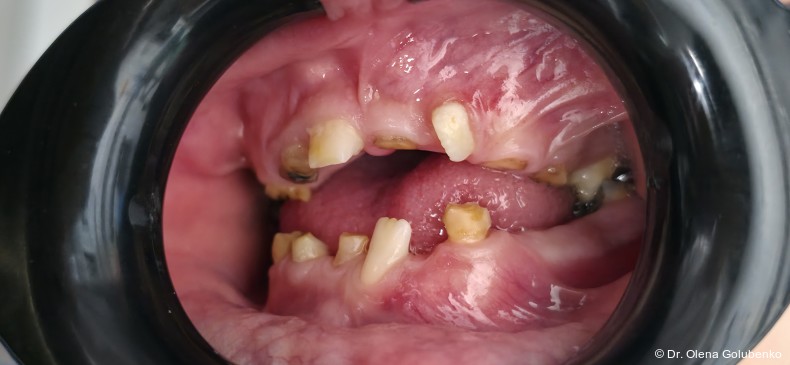

Der vorliegende Beitrag entstand aus einer kollegialen Anfrage: Eine 17-jährige Patientin mit ausgeprägten dentalen Auffälligkeiten wurde zur kieferorthopädischen Beratung überwiesen (Abb. 1a–c). Trotz zahlreicher vorangegangener zahnärztlicher Behandlungen war bis zu diesem Zeitpunkt keine syndromale Diagnose gestellt worden. Erst durch die sorgfältige Erhebung der allgemeinen und zahnmedizinischen Anamnese, die klinische Untersuchung sowie die gezielte Auswertung der dreidimensionalen Bildgebung ließ sich ein charakteristisches Muster erkennen. Auf dieser Grundlage ergab sich aus kieferorthopädischer Sicht der begründete Verdacht auf eine cleidokraniale Dysplasie, der die Vielzahl der dentalen, skelettalen und fazialen Befunde erstmals in einen schlüssigen klinischen Zusammenhang stellte.

Im vorliegenden Fall erfolgte die Überweisung durch eine zahnärztliche Kollegin mit der Bitte um kieferorthopädische Einschätzung des weiteren Vorgehens angesichts multipler nicht durchgebrochener Zähne, persistierender Milchzähne und zahlreicher überzähliger Zahnkeime.1

Das dentale Erscheinungsbild ist häufig sehr charakteristisch und erlaubt bereits früh einen Syndromverdacht. Typische Befunde sind:

• lang anhaltende Persistenz der Milchzähne

• ausgeprägte Retention der bleibenden Zähne

• multiple überzählige Zähne

• fehlende oder stark verzögerte spontane Zahndurchbrüche

• Engstände und Fehlstellungen